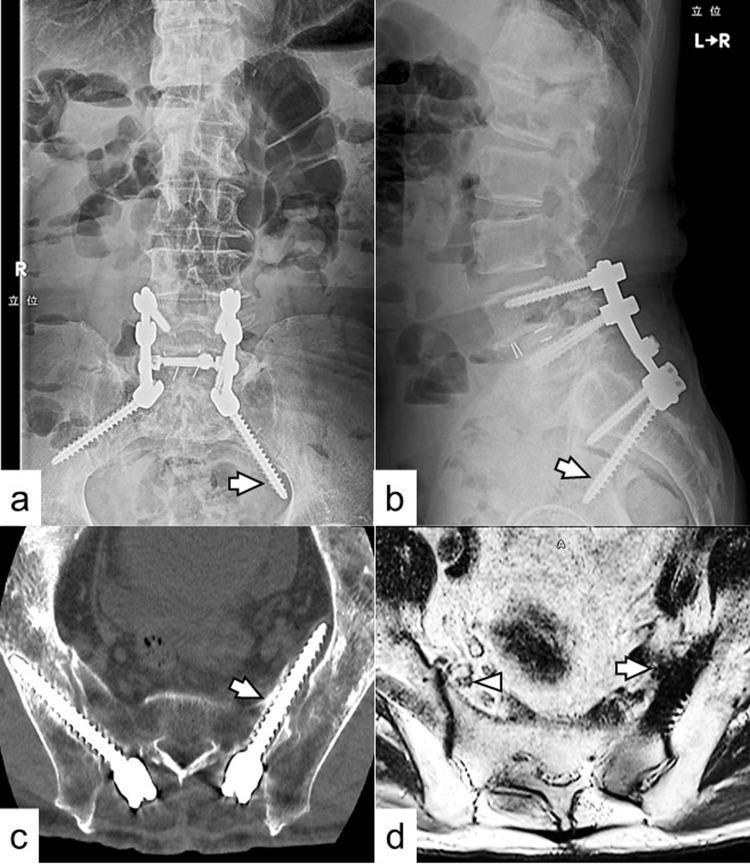

尽管在使用S2翼髂(S2AI)螺钉时,包括臀上动脉、坐骨神经、闭孔神经、髂内动静脉和腰骶丛在内的神经血管结构存在风险,但尚未有神经损伤的病例报道。一名84岁男性因之前L5-S1后路椎间融合手术深部手术部位感染,在接受使用S2AI螺钉的挽救手术后持续左下肢坐骨神经痛7个月,被转诊至我院。根据影像学和诊断性选择性神经根阻滞结果,怀疑因左S2AI螺钉尾侧移位并严重突入盆腔导致左侧L5神经根病。患者接受了左S2AI螺钉的手术置换。患者术后8天出院,左腿疼痛缓解。在3个月的随访中,未报告复发性疼痛。据我们所知,这是首例关于错位的S2AI螺钉导致L5脊神经损伤的报道病例。如果螺钉向尾侧插入并在骶髂关节前方偏离进入盆腔,在此区域走行的L5神经可能会受损。